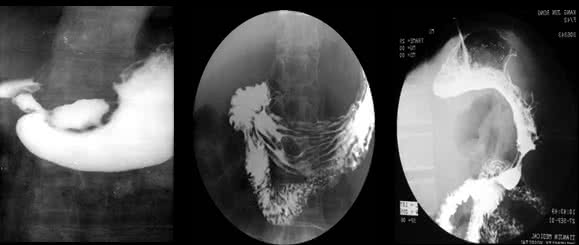

心脏造影是什么呢,说白了就是将一根很细的导管插入到我们的身体主动脉之中,然后通过在动脉中注入造影剂,通常X光的照射就能看见血管心脏的形态了。

心脏造影有冠状动脉造影和心脏(心房、心室)造影。冠脉造影就是用一根细如发丝的导管沿着桡动脉(手腕处)或股动脉(大腿处)的人为入口延行到心脏的冠状动脉开口处,然后把造影剂(在X光下显影)注入冠状动脉,这样冠状动脉内部的形态就可以显示出来,例如看冠脉有没有狭窄、斑块等,但基本上不能通过这个检查来了解心脏形态的,主要还是了解冠脉的内部形态及冠脉内的血流速度。